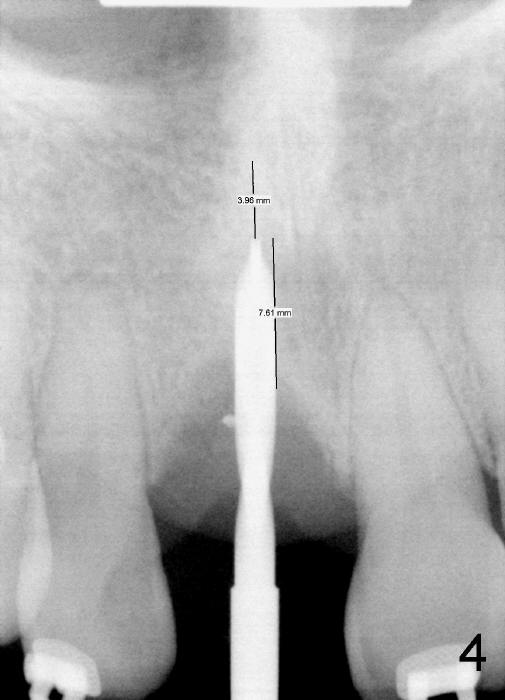

Osteotomy starts in the palatal aspect of this shallow socket with 2 mm pilot drill (Fig.4). New bone is gained 7.61 mm; another 3 mm is to be planned for primary stability.